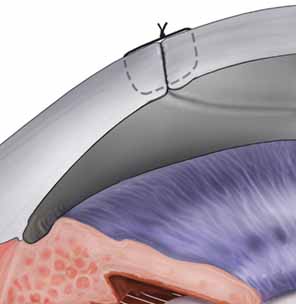

LAMELLAR KERATOPLASTY

DEEP LAMELLAR KERATOPLASTY